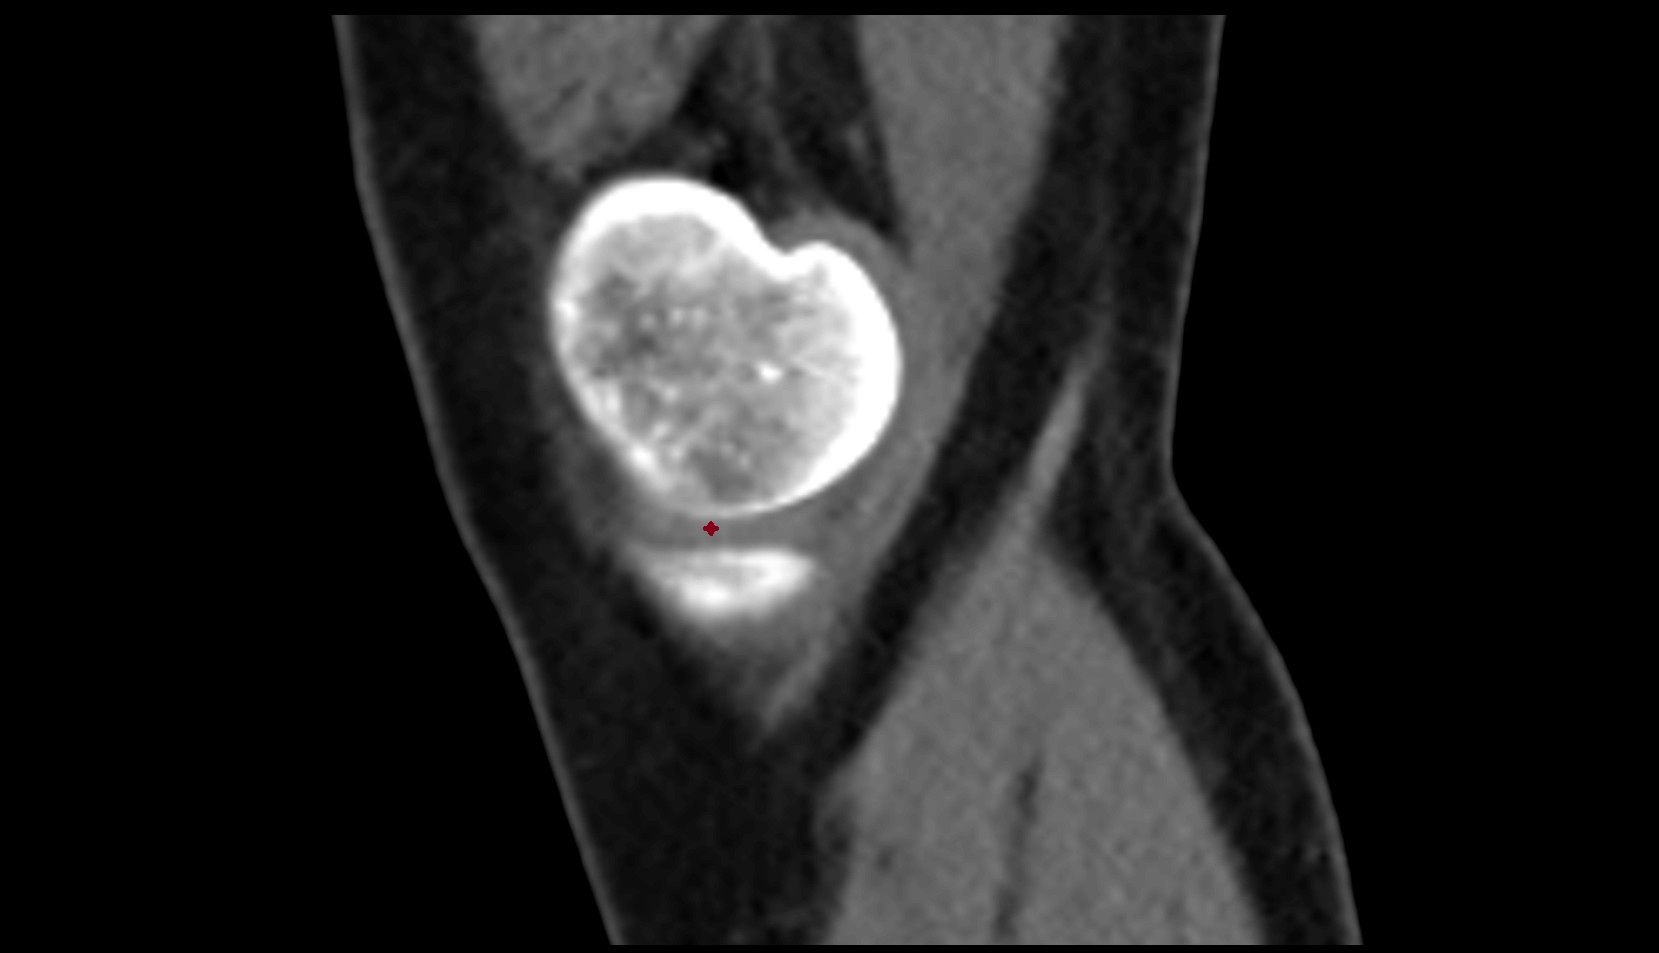

- Patella